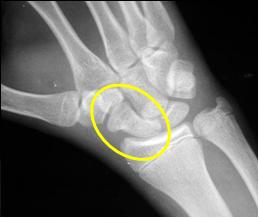

You need a scaphoid

view to be certain!